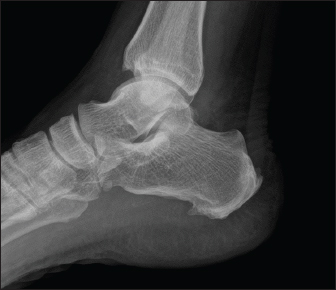

Patient 3

A 75-year-old male with a history of diabetes mellitus presented with a 3-week history of fever and left shoulder pain, back pain and leg pain. He reported no recent travel or exposure to known environmental sources of B. pseudomallei. Physical examination revealed erythema and tenderness over the left shoulder and tenderness over right foot and over the dorsal spine. Radiographs showed features fitting with osteomyelitis of left humerus. By the time blood cultures grew B. pseudomallei. X-ray foot (Fig. 4) taken showed osteomyelitis changes. The patient was diagnosed with osteomyelitis caused by melioidosis and was treated with intravenous ceftazidime and doxycycline for 6 months, followed by oral cotrimoxazole for another 6 months. The patient had a good recovery and was followed up in the out-patient clinic.

Fig. 4. Xray foot—patient 3.